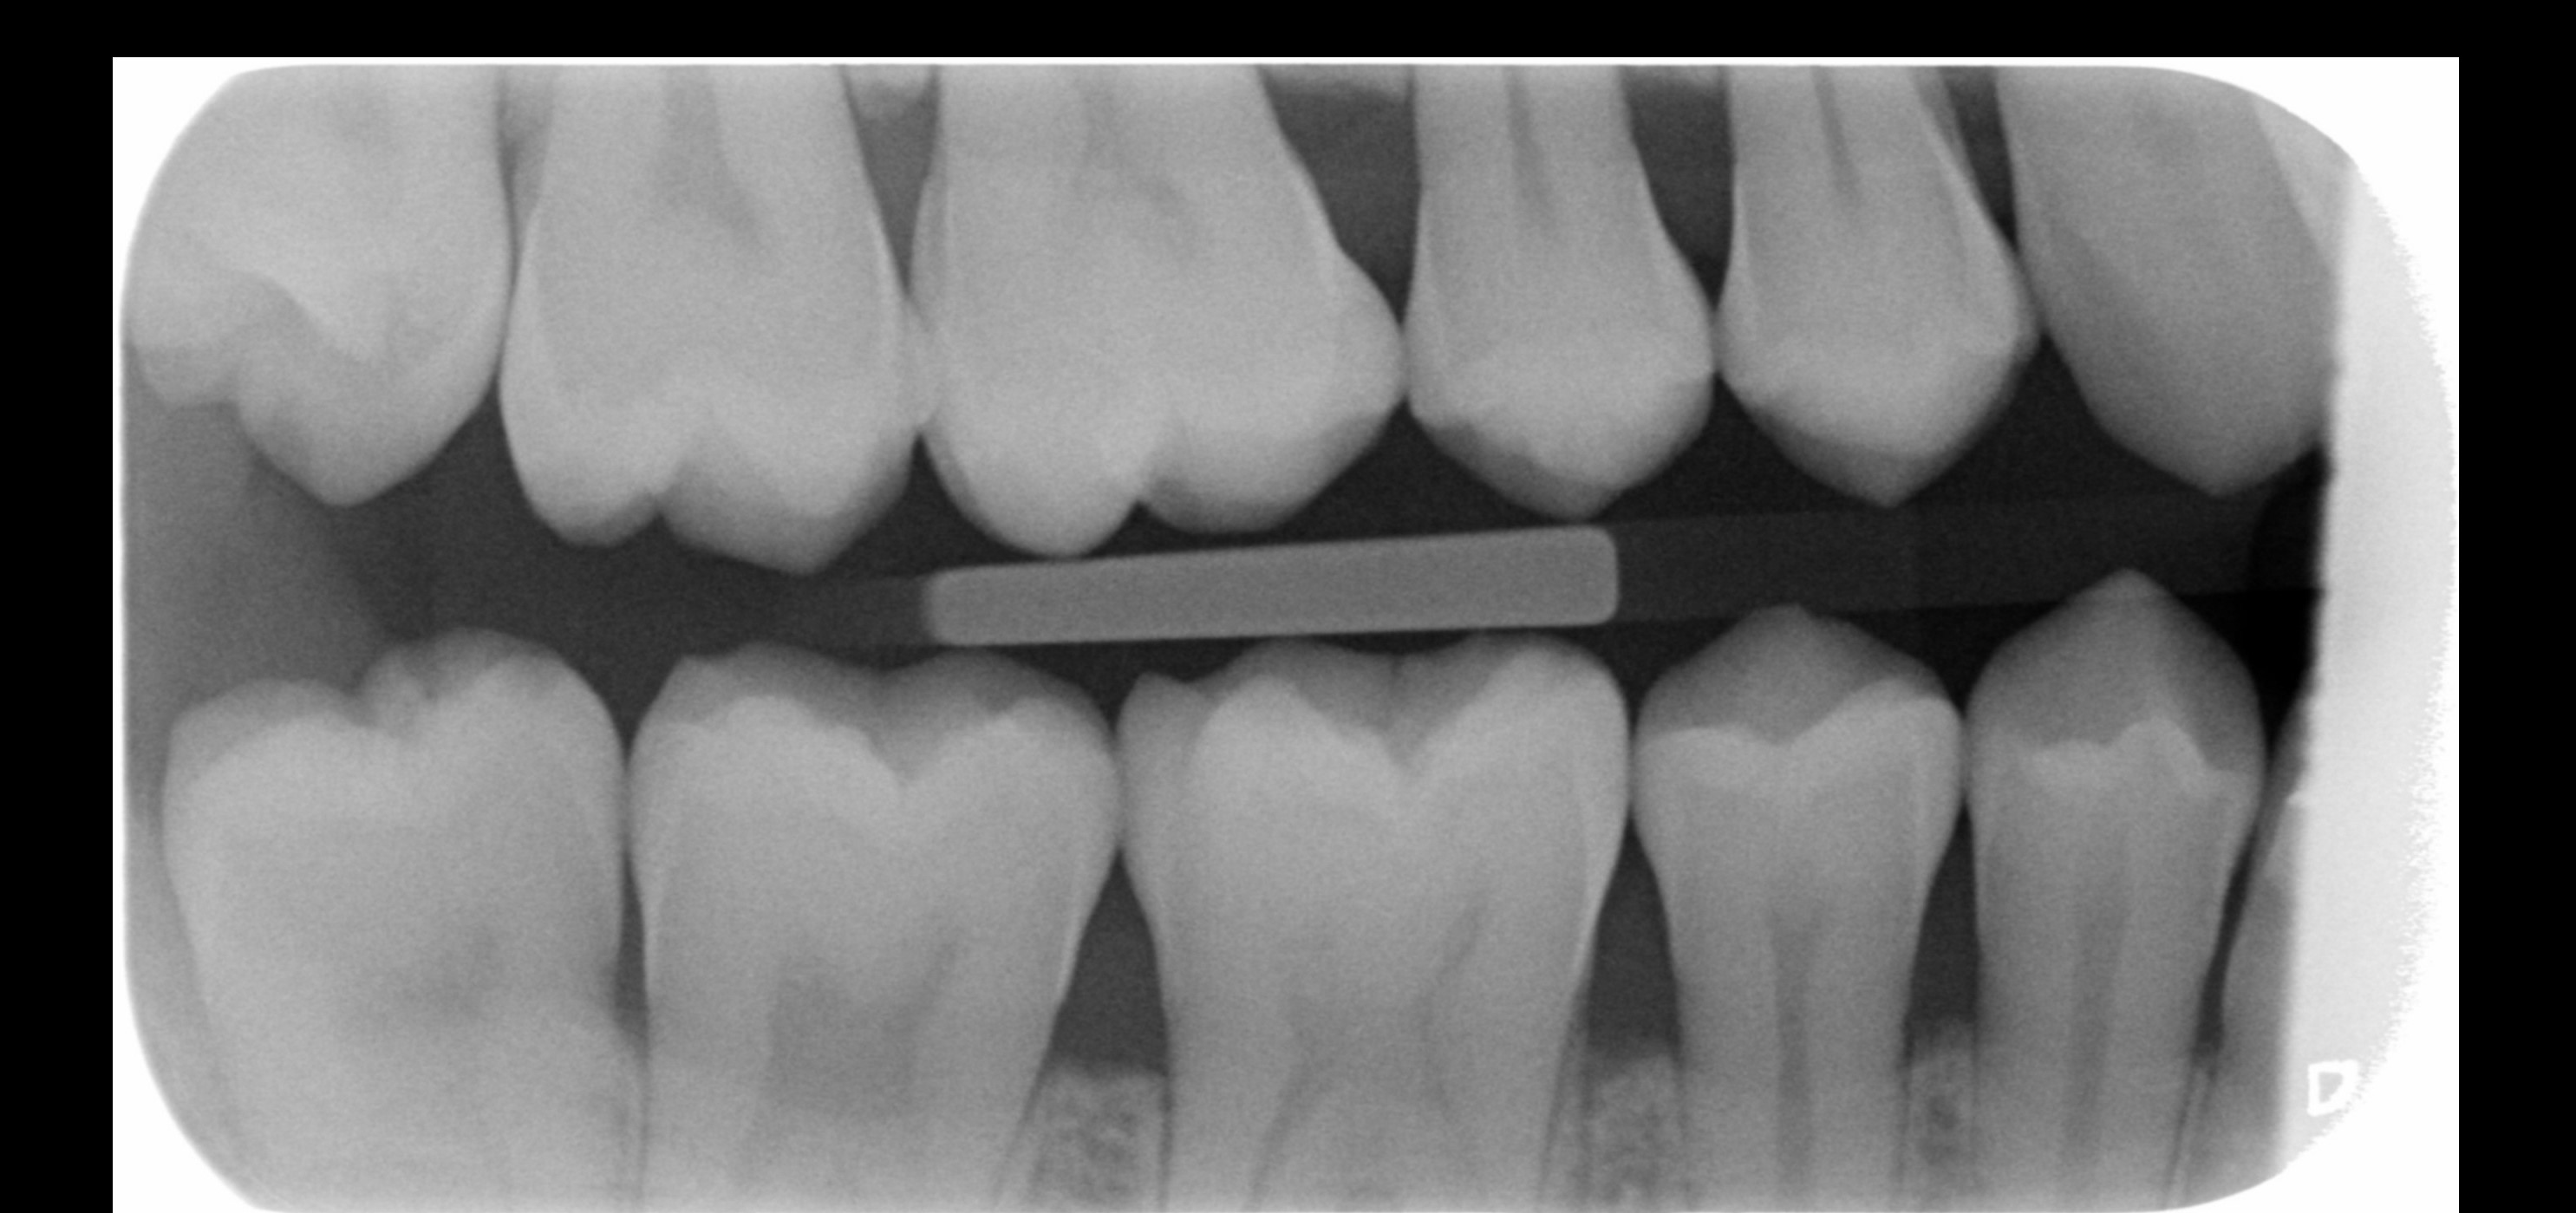

Heb al circa een week last van pericoronitis (wel vaker gehad). Deze keer duurt de genezing wat langer. Pijn is helemaal weg, maar het tandvlees daar is nog zacht en niet strak tegen de verstandskies. Foto 1 is hoe het nu is, zacht tandvlees, en foto 2 toen het gezond was waarbij het tandvlees strak is. Wanneer zal de zachtheid weggaan? Ik spoel al dagelijks met zoutwater. Ben ook van plan om in 2026 mijn verstandskiezen te verwijderen. Foto 3 en 4 zijn foto's van mijn verstandskiezen, heb alle 4 al meer dan 12 jaar niet laten trekken, maar denk dat ik het beter kan doen? Werd wel vaak gezegd tegen me dat het slim is om ze te laten trekken, maar ik ben altijd bang van zulke behandelingen.

Ik had in april dit jaar al een vraag gesteld in dit forum over mijn mogelijke erosie, u gaf toen aan dat er enige slijtage was. Ik heb totaal geen idee hoe het kan zijn ontstaan, omdat ik mijn hele leven al zowat geen suikers of prik of zure dranken nuttig. Mijn tandartsen en mondhygienisten hebben er ook NOOIT wat over gezegd. Hierbij een foto van 2015 en 2025 onderkaak tanden. Ik zie in die 10 jaar geen verschil. Is het echt flinke slijtage of valt het mee? Wat betreft mijn botniveau, heb ik inderdaad te horen gekregen dat er sprake is van lichte botafbraak, ik gebruik nu elke dag ragers. Heb in het verleden ook een beugel gehad, zou dat ook voor veranderingen in het bot kunnen zorgen? x-fotos van mijn rechter kaak uit 2010 en eind 2024.

Bovenste x-foto lijkt meer dan onderste foto maar kan ook aan de inschiet richting liggen.